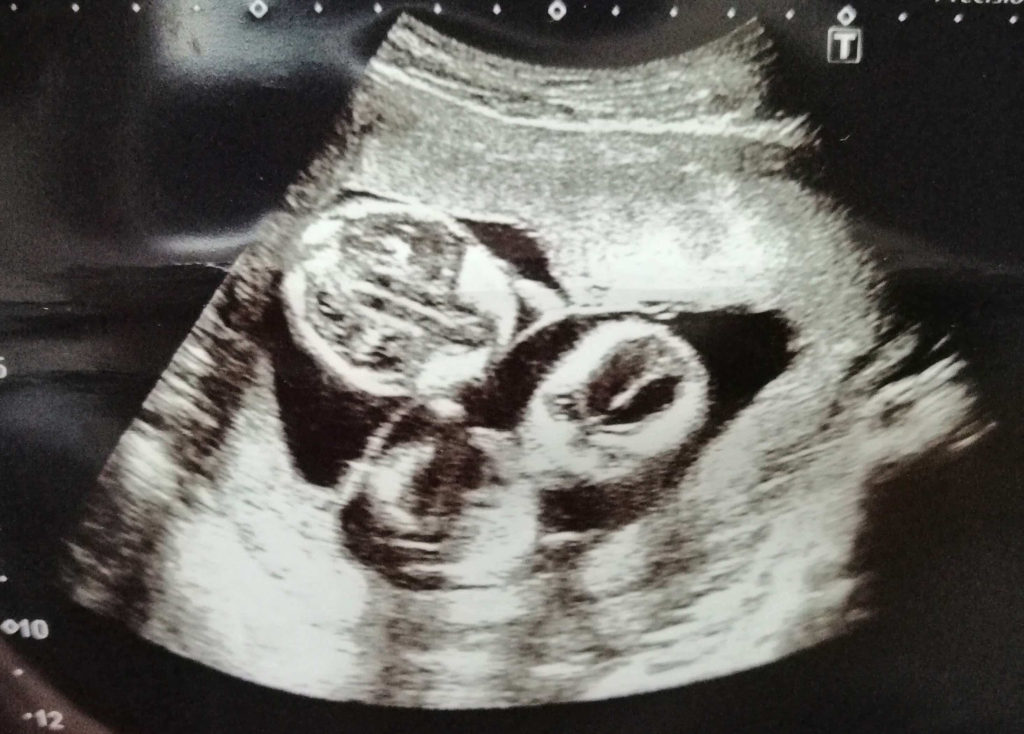

◆エコー

私が双子妊娠5ヶ月(16週)の時の赤ちゃんのエコーです。

2人揃ってエコーに映ることが出来るのは5•6ヶ月頃までですので2人がしっかりと写っている良い写真を撮ってもらいましょう。

顔つきが人間らしくなり、大きくなってきています。

5ヶ月は性別も判明する頃です。医師から上の画像を見て「女の子かもね!」と言われました。